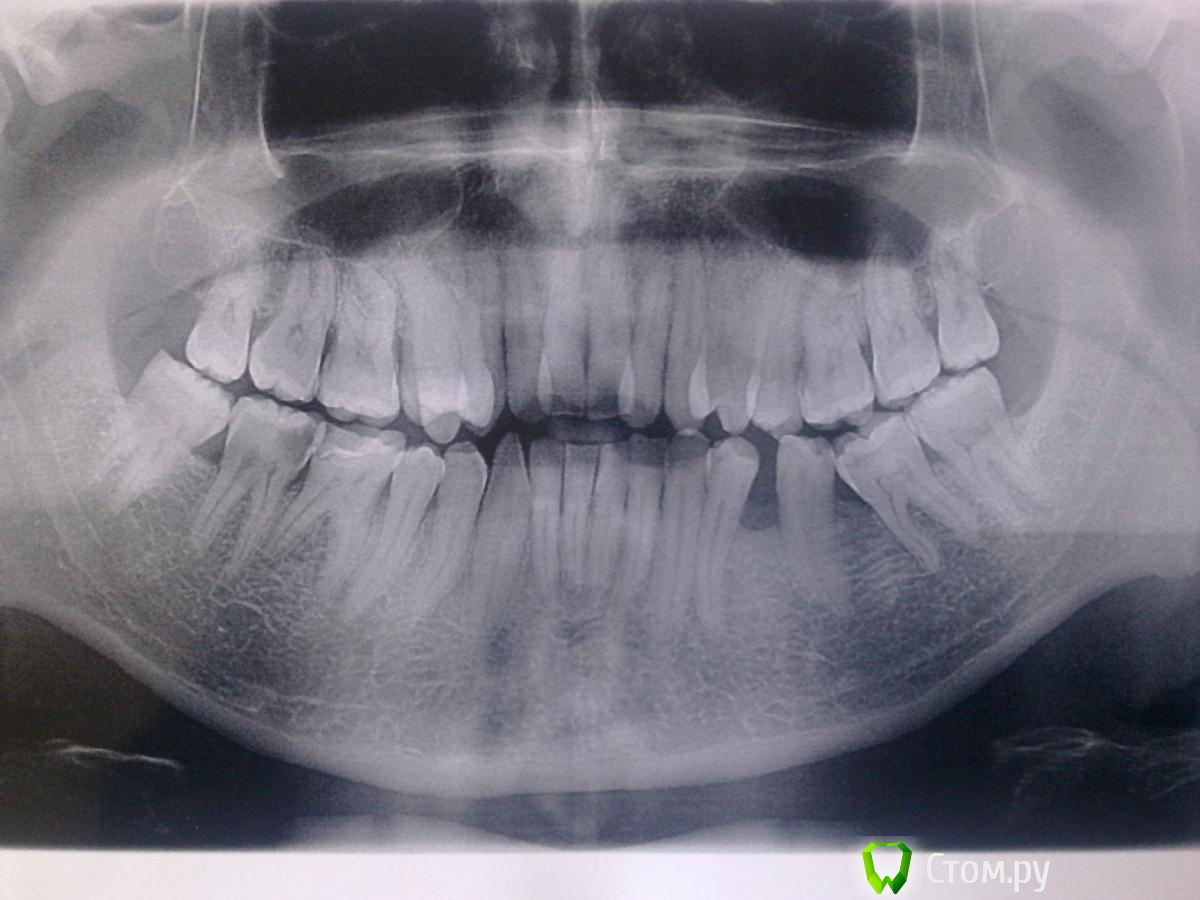

Илья_ Опубликовано 6 ноября, 2014 Поделиться Опубликовано 6 ноября, 2014 Предыстория:31 год. Но очень боюсь посещения стоматолога. После нескольких не очень удавшихся попыток дойти лечить зубы обычным способом (просто становится плохо как захожу в кабинет, хоть стреляйся, хотя вроде и не маленькое дите и понимаю, что сейчас уже не такие технологии и инструмент как 10-15 лет тому назад, но даже просто на консультацию зайти проблемма, не только стоматологов, а вообще врачей ). Решился на лечение под общим наркозом. До этого не посещал стоматолога порядка 10-12 лет... Обидно, досадно, но как есть.. Решился, потому как летом заметил что появилась "дырка" справа внизу в 7м зубе. Внушительная такая.. Появилась как-то очень быстро. Беспокойств особых не приносила, но на мозги капала, что нужно идти. Вроде немного поднывал этот зуб, а может это больше психологически, не могу сказать на 100%. Перестал на этой стороне жевать, хотя раньше жевал практически исключительно на правой. Сделал снимок, чтобы врачу было проше и нацелился идти! Врача и клинику выбрали по многочисленным рекомендациям, в том числе и рекомендациям стоматологов, которые работают в других клиниках (немного знакомые) где не делают общего наркоза. Все отправили к этому врачу. Врач опытная, не малый стаж в этой сфере, порядка 22 лет и т.д. и т.п... В итоге:20 октября, наконец-то добрался я до стоматолога.Пролечили мне под общим наркозом 7 зубов, в том числе перепломбировали единственную на тот момент в моем рту пломбу. Все зубы остались живые. Заняло это у врача порядка 1,5 часов. Все обошлось, как мне сказали, лишь кариесом. Первый день было все просто отлично. Радовался жизни так сказать! Потом, к вечеру второго дня как-то разнылся весь рот. Возможно после жевания на ужин жесткого. Утром уже все было в норме, ничего не болело. Стал снова чаще жевать на правой стороне. Получается примерно на третиц день после лечения появилась ноющая боль справа снизу. Самое интересное, что я не могу конкретно сказать, какой из зубов беспокоит. Больше склоняюсь к 6му, который ранее был запломбирован и еоторый перепломбировали, хотя может и 7... А может даже 5 или 8 ... Чес слово - непонятно. 65%, что 6ой. Что интересно - на горячее / холодное реакции нет, не болит, попробовал немного постукивать по этим зубам - тоже никакой болезненной реакции. С утра, как правило, ничего НЕ ноет, к вечеру реально танущая, несильная, ноющая боль. Когда что-то ешь, жуешь на этой стороне, то наоборот!!! Не больно, а наоборот хорошо становится. Только если очень что-то жесткое - тогда есть чувствительность толи в 6, толи в 7....Позвонил врачу - сказала пропить немисил, пропил порядка 4х дней - ничего не поменялось. Сегодня уже 16ый день после лечения, ощущения теже. Сильнее не становится вроде, но и не проходит. Если бы еще не проблемма посетить очно, но одно, а для меня это проблемма.. В кратце:Боль не сильная, но до ужаса неприятно ноющая. Жевать НЕ больно, надавливать не больно, постукивать не больно.. Очень странно. Наоборот, когда что-то ешь, то полный комфорт.... Начинает ныть к вечеру. И как раз когда ничего не жуешь, НЕ ешь... На холодное, горячее, кислое, сладкое - никаких болезненных ощущений не происходит... Прилагаю снимок до лечения , снимок после лечения (оригинал, полученный на диски и скриншот при просмотре в CliniView):http://s017.radikal.ru/i432/1411/9d/3385f7e48847.pnghttp://s55.radikal.ru/i148/1411/f7/c1ae923b2494.png Заранее спасибо. Ссылка на комментарий